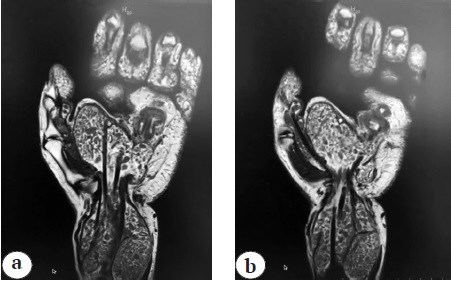

MRI was performed on June 26, 2022 (Magnetom Skyra 3T, examination protocol: T2 COR, T1 COR, T1 COR FS, PD COR FD, PD TRA FS, PD SAG FS). Detected: MR image of peritendinous, synovial, cystic formation along the palmar surface of the hand, wrist joint with the presence of multiple cartilage flaps. The above mentioned changes were most typical for the manifestation of synovial chondromatosis. Edematous changes in the surrounding soft tissues, tendinitis, tenosynovitis of the flexors of IV, V fingers of the hand were also observed. In addition, peritendinous synovial cyst of the hand was found, located subcutaneously, in the area of IV finger, communicating with the synovial sheath (Fig. 2).

Fig. 2. MRI scans of right upper extremity: a — masses on the volar surface of the hand and wrist joint with multiple chondromal bodies, «rice grains» inclusions; b — peritendinal synovial cyst, located subcutaneously in the IV ray area, communicating with the flexor channels